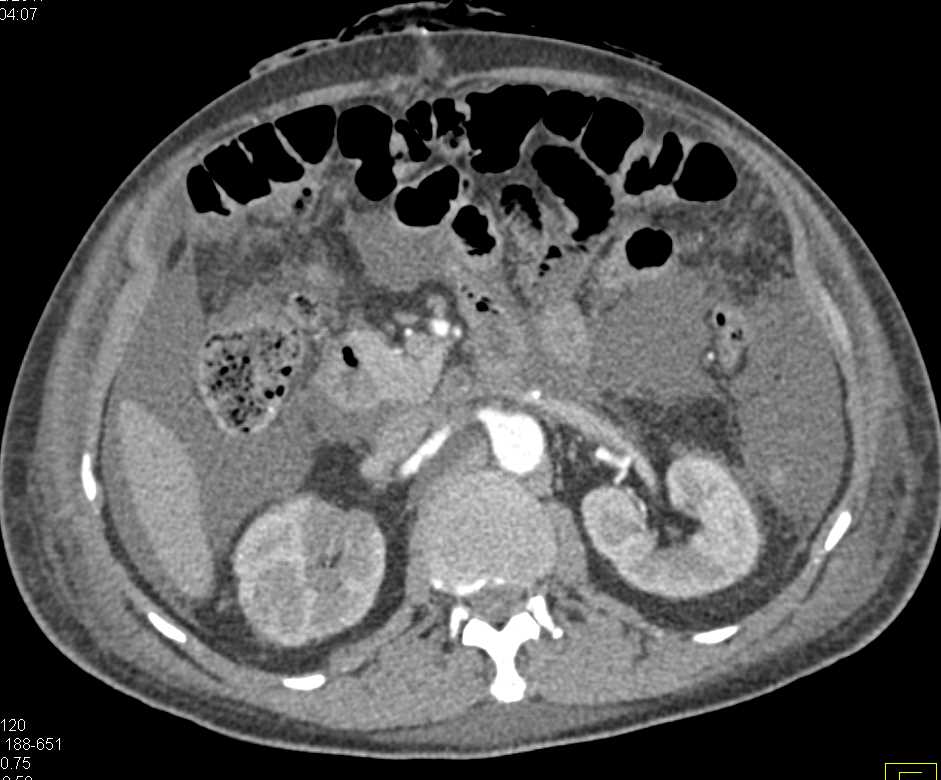

Ovarian Cancer with Carcinomatosis